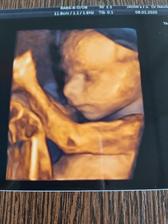

Druhé šťastie